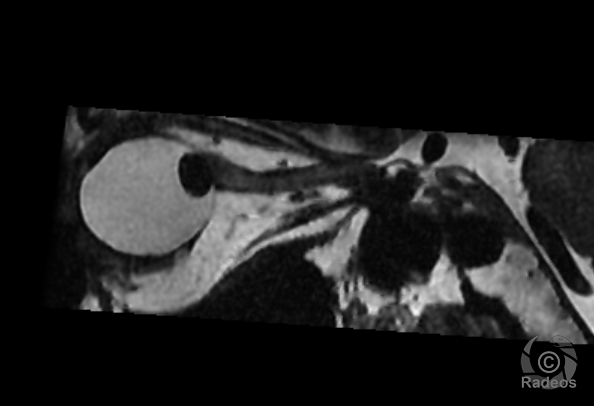

LE CAS DU MOMENT

Aspect IRM d'une fibromatose profonde de la paroi abdominale. Découverte fortuite d'un angiome hépatique gauche.